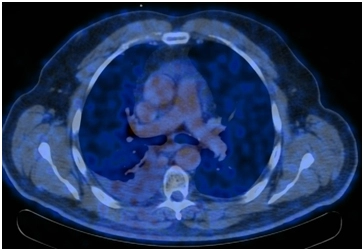

ПЭТ/КТ от 31.05.2017. Отмечается положительная динамика в виде нивелирования центрально расположенного образования нижней доли правого легкого и медиастинального лимфоузла. Постлучевой фиброз, ателектаз нижней доли правого легкого. Умеренно выраженный правосторонний гидроторакс. Повышение метаболизма в кардиальном отделе пищевода – постлучевой воспалительный процесс.

ПЭТ/КТ 04.08.2017. На момент исследования по данным ПЭТ/КТ с 18F-ФДГ признаков патологического метаболически активного процесса, обусловленного основным заболеванием не выявлено.

Постлучевой фиброз, ателектаз нижней доли правого легкого.

Умеренно выраженный правосторонний гидроторакс (увеличение в динамике).

Метаболически активного процесса в кардиальном отделе пищевода на момент исследования не выявлено.